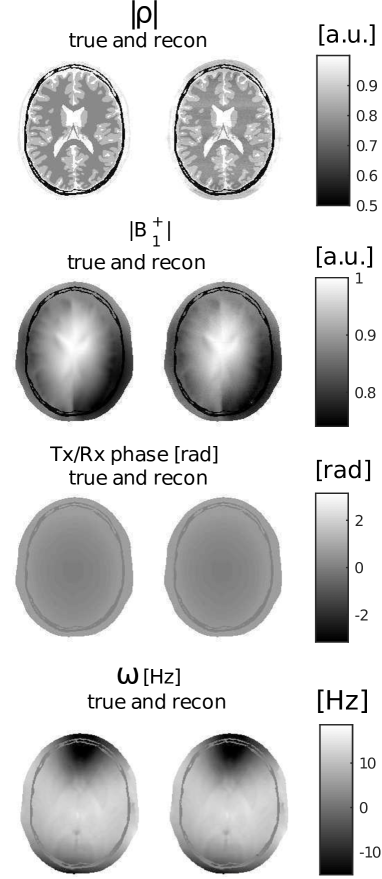

Beside T1subscript𝑇1T_{1}, T2subscript𝑇2T_{2} and ρ𝜌\rho, also the transmit field profile and off-resonance map are reconstructed; they are displayed in Figures 6 and 7. They closely agree with the true values. In Table 2, the mean values and corresponding variations over each tissue type are reported and show high precision.

The root-mean-squared-errors (RMSE) for the B1+superscriptsubscript𝐵1B_{1}^{+} and ω𝜔\omega maps are also very small, namely:

RMSE(|B1+|)=0.0043 [a.u.],RMSE(ω)=0.12 [Hz].formulae-sequenceRMSEsuperscriptsubscript𝐵10.0043 [a.u.]RMSE𝜔0.12 [Hz]\text{RMSE}(|B_{1}^{+}|)=0.0043\text{ [a.u.]},\quad\text{RMSE}(\omega)=0.12\text{ [Hz]}.

The standard deviations estimated by MR-STAT for T1subscript𝑇1T_{1} and T2subscript𝑇2T_{2} are shown, respectively, in Fig. 6(b) and Fig. 6(d). For comparison, the actual error maps, respectively defined as |T1T1recon|subscript𝑇1superscriptsubscript𝑇1recon|T_{1}-T_{1}^{\mathrm{recon}}| and |T2T2recon|subscript𝑇2superscriptsubscript𝑇2recon|T_{2}-T_{2}^{\mathrm{recon}}|, are also reported and they show clear similarities.

Figure 6: T1subscript𝑇1T_{1} and T2subscript𝑇2T_{2} maps for the synthetic MR-STAT acquisition and reconstruction. (a) and (c): true and reconstructed maps. (b) and (d): standard deviation maps estimated by MR-STAT and the error in the reconstructions (|T1trueT1recon|superscriptsubscript𝑇1truesuperscriptsubscript𝑇1recon|T_{1}^{\text{true}}-T_{1}^{\mathrm{recon}}| and |T2trueT2recon|superscriptsubscript𝑇2truesuperscriptsubscript𝑇2recon|T_{2}^{\text{true}}-T_{2}^{\mathrm{recon}}|).

Figure 7: True and reconstructed maps of proton density, transceive phase, |B1+|superscriptsubscript𝐵1|B_{1}^{+}| and ω𝜔\omega.